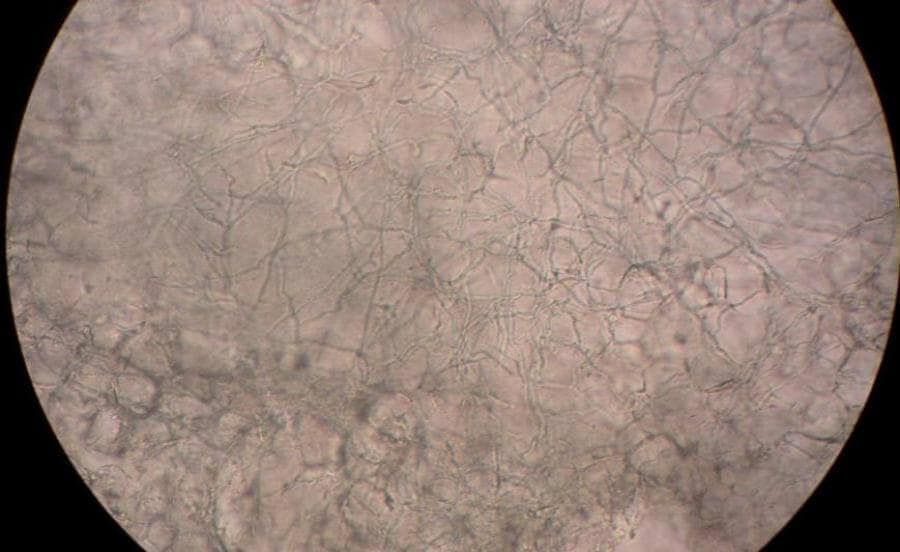

Een schimmelinfectie aan de voeten komt regelmatig voor. De infectie ontstaat vaak tussen de tenen, maar kan ook op de voetzool en/of aan de randen van de voet optreden. Voetschimmel is te herkennen aan specifieke klachten. Deze soort huidschimmel is gelukkig goed te behandelen. Bovendien kun je maatregelen nemen om een schimmelinfectie aan de voeten te voorkomen.

Eczeem aan de voeten kan ook lijken op voet schimmel. Een schimmel veroorzaakt namelijk, net als eczeem, een rode huid, schilfering en jeuk. Op zowel de voeten als de huid tussen de tenen. Toch zijn er een aantal belangrijke verschillen tussen beide huidklachten, waaronder de oorzaak.

Verder uit voetschimmel zich met name als: rode voetzolen, jeuk, witte schilfering en kloofjes. Een typisch kenmerk hierin is de ringvormige schilfering. Dit is bij eczeem niet het geval. In enkele gevallen kan de schimmel ook voor blaren, kleine blaasjes of puistjes zorgen.

Een ander belangrijk verschil tussen voetschimmel en voeteczeem is dat het bij voetschimmel gaat om een huidinfectie. Terwijl eczeem het gevolg is van een huidontsteking. Veroorzaakt door erfelijke aanleg, irriterende stoffen en/of hevige emoties zoals stress. Ondanks deze verschillende oorzaken, geven beide huidklachten wel vergelijkbare klachten.

Daarom wordt voetschimmel ook wel zwemmerseczeem genoemd. Toch is het niet helemaal terecht dat de huidklacht zwemmerseczeem genoemd wordt. Zwemmerseczeem, oftewel voetschimmel, is namelijk helemaal geen vorm van eczeem. Maar een schimmelinfectie van de huid.